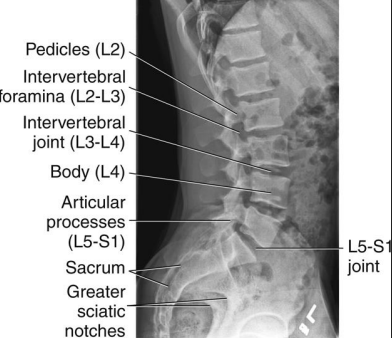

Lateral L-Spine: Eval Criteria

Centered at the crest to include T12 to sacrum

Spinal column aligned parallel to the IR

No tilt

No rotation

Rotation Lateral L-Spine

Separated posterior vertebral bodies

Spinous process shifted to the right of midline = slight LPO

Tilt (or ____) Lateral L-Spine

Sagging

Indicated by closed intervertebral foramina and joint spaces